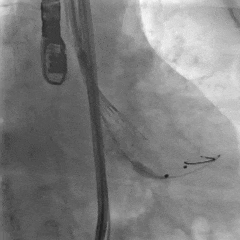

TEE长轴:瓣膜深度可

TEE短轴:瓣膜展开良好,仅少量瓣周漏

-

主瓣峰值流速由术前4.2m/s降至术后1.69m/s

主瓣峰值压差由术前70mmHg降至术后11mmHg